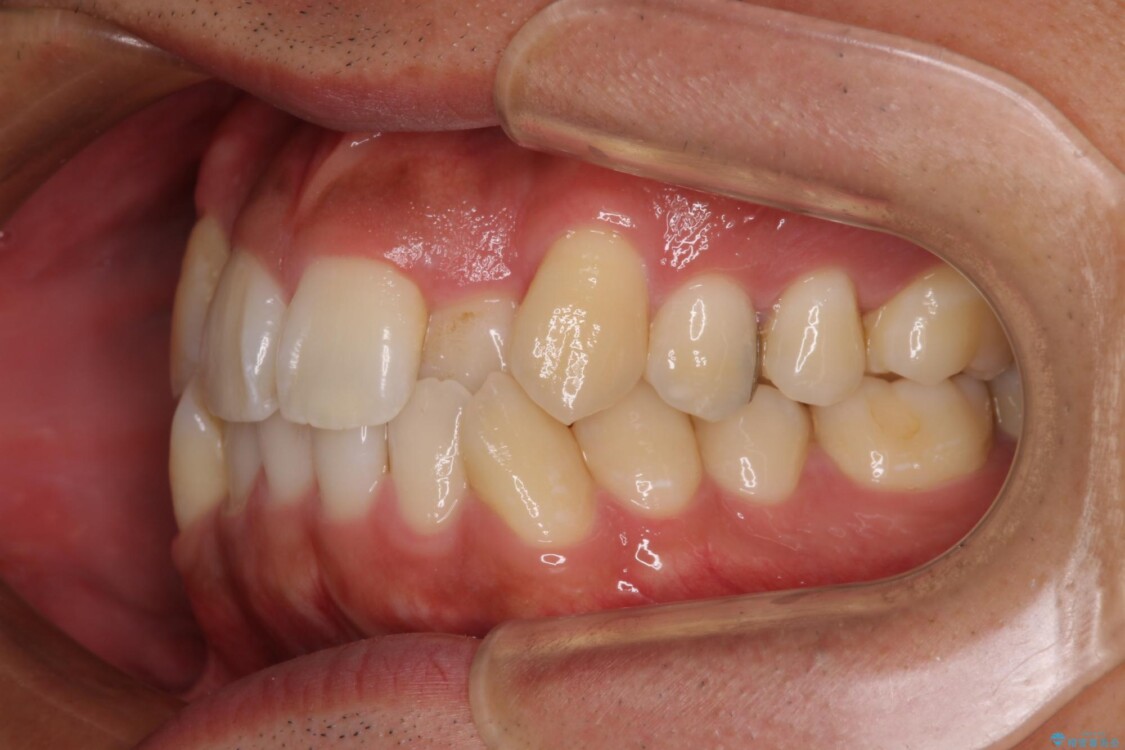

「八重歯を治したい」とご相談いただいた患者様の症例をご紹介します。

上下の前歯部に強い叢生(ガタガタの歯並び)があり、そのまま歯を並べると出っ歯になってしまう可能性がありました。

治療前

• 八重歯と前歯のガタガタを抜歯矯正で治療|クリアブラケット使用例 治療前画像